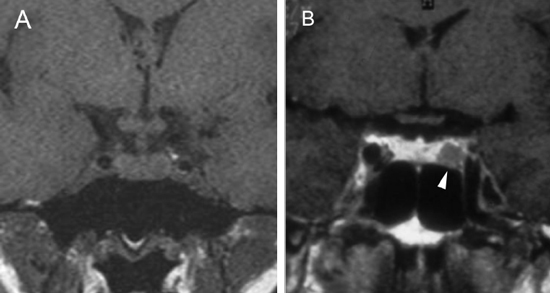

En los tumores grandes (macroadenomas) la TAC puede entregar información diagnóstica adecuada, pero no supera la definición que se logra con equipos de RM superconductores (Figuras 2 A y 2B).

Figura 2A y B. Cortes sagitales de RM y TAC. Adenoma pituitario con invasión del esfenoides y del clivus (puntas de flecha). Es posible demostrar las estructuras óseas en RM con similar precisión que la TAC.